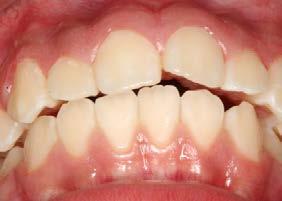

Introducción: La maloclusión clase II provoca proporciones irregulares en el perfil facial. Puede deberse a un maxilar adelantado y a incisivos superiores proinclinados y protruidos. Esta condición puede corregirse mediante el uso de aparatos ortopédicos en pacientes en crecimiento.

Objetivos: Conseguir clase I canina, controlar el crecimiento vertical, disminuir la convexidad esqueletal, reducir la sobremordida horizontal y mejorar el perfil facial. Caso clínico: Paciente femenina de 9 años, clase II esqueletal, biotipo dolicofacial, perfil convexo, clase II molar, clase II canina y proinclinación de incisivos superiores e inferiores. Resultados: Se logró clase I canina, se controló el crecimiento vertical, se redujo la convexidad esqueletal, se mejoró la sobremordida horizontal y el perfil facial. Conclusiones: El uso combinado de aparatos ortopédicos y aparatología fija en pacientes en crecimiento, junto con un diagnóstico y plan de tratamiento acertado, permite obtener resultados exitosos y estables en la corrección de estas maloclusiones.

La relación maxilomandibular desempeña un papel importante en la posición de los molares y puede clasificarse como clase I, II o III, de acuerdo con la clasificación de Angle. Esqueletalmente, esta relación solo puede determinarse mediante estudios radiológicos; los modelos de estudio solo ofrecen una aproximación clínica.1